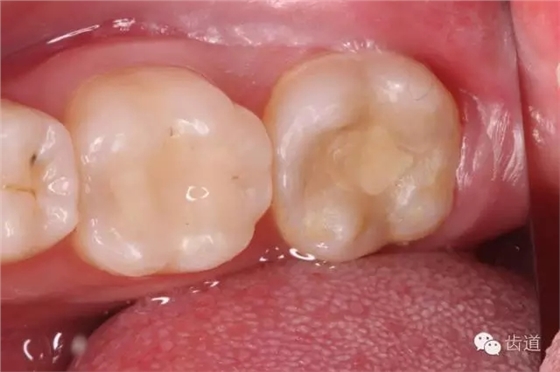

1. 暫封保存完好

2. 去盡暫封及原充填物,發(fā)現(xiàn)近中頰側(cè)壁較薄,有無(wú)基釉殘余